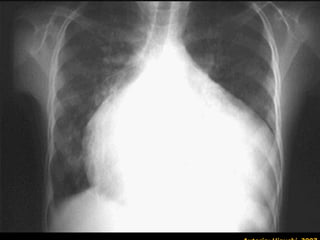

Caracterizada por miocardite difusa, com vários graus de severidade. Podendo ocorrer:  ♦  Pericardite ♦  Cardiomegalia ♦  Insuficiência Cardíaca Manifestações mais comuns Febre prolongada e recorrente Cefaléia Mialgias Astenia Hepatomegalia Ascite Esplenomegalia

Caracterizada por miocarditedifusa, com vários graus de severidade. Podendo ocorrer: ♦ Pericardite ♦ Cardiomegalia ♦ Insuficiência Cardíaca Manifestações mais comuns Febre prolongada e recorrente Cefaléia Mialgias Astenia Hepatomegalia Ascite Esplenomegalia